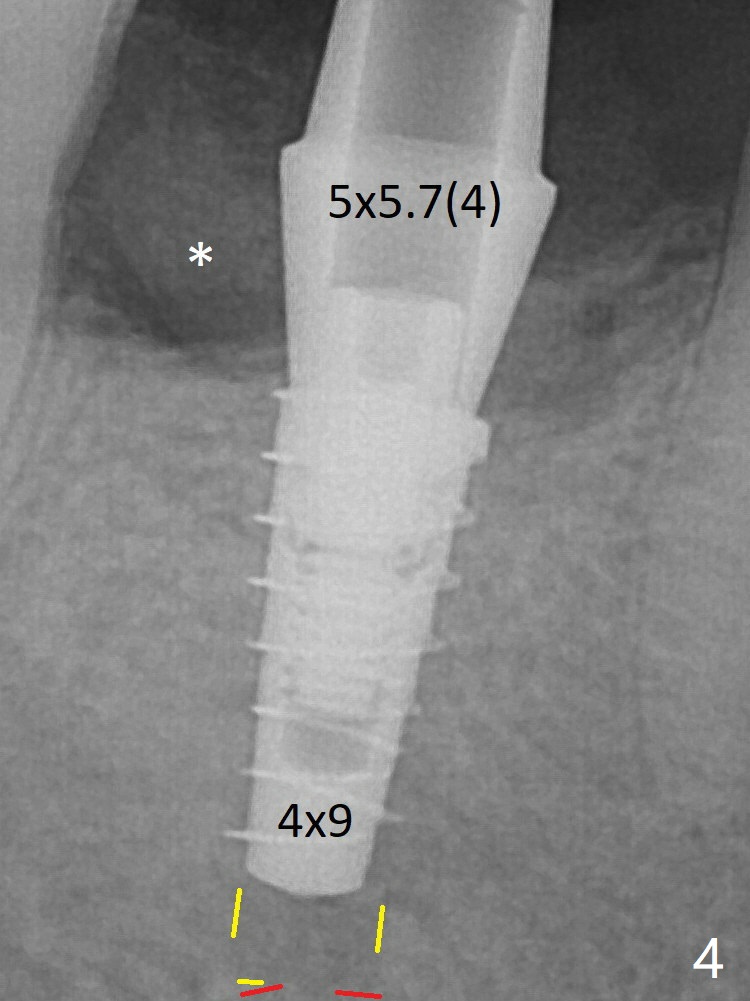

For safety, a 4x9 mm IBS implant is placed with insertion torque 40 Ncm; a 5x5.7(4) mm abutment is immediately placed for an immediate provisional to cover the large socket and keep Vera graft in place (Fig.4 *). Yellow dashed line: apical osteotomy; red dashed line: Mental Loop. Impression is taken nearly 3 months postop (Fig.6). The bone density around the implant increases 7 months post cementation (Fig.8 *). The higher density bone seems to extend coronally 1 year 7 months post cementation (Fig.9).